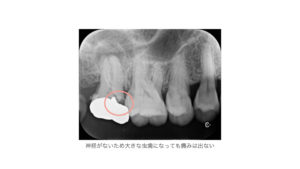

しかし、神経を抜いてしまうと、歯が外敵を感知するための能力を失ってしまうため、仮に大きな虫歯ができてしまっても症状が出ることはありません。

何か違和感を感じてレントゲンを取ると歯を抜かないといけないくらいの虫歯ができていることもあります。